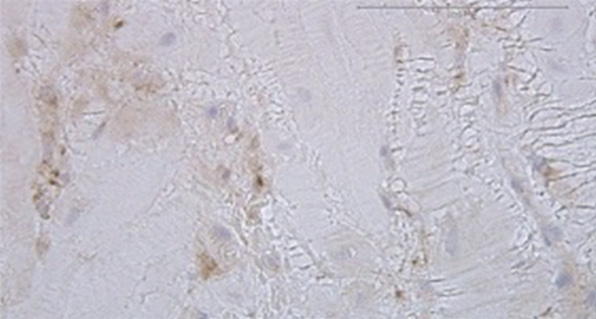

При микроскопическом исследовании гистологических препаратов группы сравнения без клинических признаков врастания плаценты визуализированы фрагменты гладкомышечной ткани с пучками коллагеновых волокон, крупноочаговыми кровоизлияниями. Однако в ткани рубца обнаружены клетки трофобласта, расположенные линейно и мелкоочаговыми скоплениями (рис. 2, c). В биоптатах данной группы найдены фрагменты децидуальной ткани с мелкоочаговой периваскулярной мононуклеарной инфильтрацией, не обнаруженные в группе пациенток с рубцом на матке и ПАИП (рис. 2, d).

Рис. 2. Микрофотографии биоптатов миометрия из маточно-плацентарной области: a — ворсина хориона в биоптате миометрия при плацентарной адгезивно-инвазивной патологии (PAS 3a–c); b — децидуальная оболочка в биоптате миометрия при плацентарной адгезивно-инвазивной патологии (PAS 3a–c); c — фрагмент миометрия группы сравнения с полнокровием капиллярного русла из области прикрепления плаценты; d — фрагмент миометрия группы сравнения с участком децидуальной ткани из области прикрепления плаценты; e, f — фрагмент миометрия контрольной группы с участком децидуальной ткани. Окраска гематоксилином и эозином, увеличение ×200